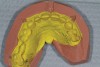

Figure 1  The proposed gingival alteration marked on the cast.

Figure 1

Figure 2   Laboratory alteration of the gingival contours in the diagnostic wax-up.

Figure 2

3. Lack of Direction on Tooth Positioning and Gingival Alteration

Practitioners must inform the laboratory of the proper amount of incisal edge addition. This decision must be made in the operatory during repose, smiling, and speaking. Robbins has outlined many of these principles.17 These are not static choices that can be made on mounted casts. While photographs of the patient are important for the laboratory, the ultimate decision should rest with the restorative dentist. In addition, if surgical alteration of the gingival architecture is planned, clinicians should mark proposed surgical alteration of the gingival levels on the casts. The laboratory can adjust the stone to mimic the change on the diagnostic wax-up (Figure 1 and Figure 2).